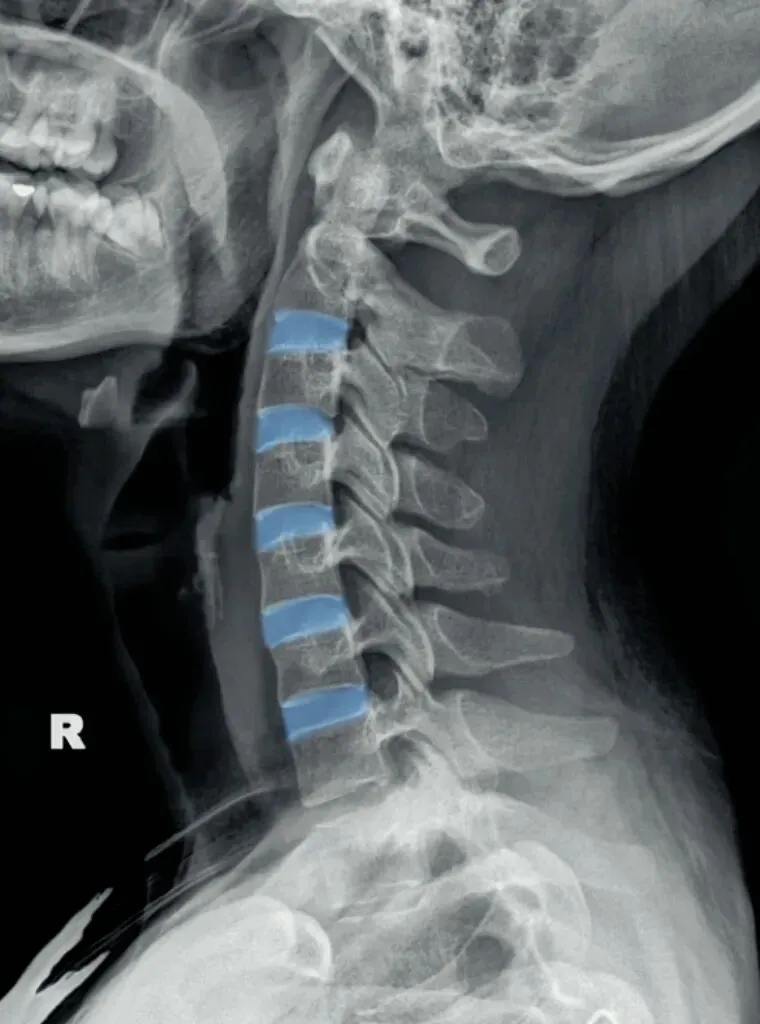

二弓指的是颈椎生理曲度,在颈椎侧位X线片中,正常生理状态下呈现向前凸出的弧形曲线,呈半C型前凸类似弓形,是人体脊柱生理曲度的重要组成部分。颈椎曲度变化能够反映颈椎整体功能的变化。

常见的颈椎曲度改变有曲度变直和曲度反曲。

颈椎生理曲度测量的方法多种多样,其中应用最广泛的测量方法是Borden法。从齿状突后上缘开始向下将每个椎体后缘相连成为一条弧线,然后从齿状突后上缘至C7椎体后下缘作一直线测量,两条线间最宽处的垂直横交线的距离即为颈椎生理曲度深度。

正常时,最宽处在C4椎体水平正常为12毫米,正负5毫米,小于7毫米为生理曲度变直,大于17毫米为生理曲度过度前屈,小于零时为生理曲度反曲。